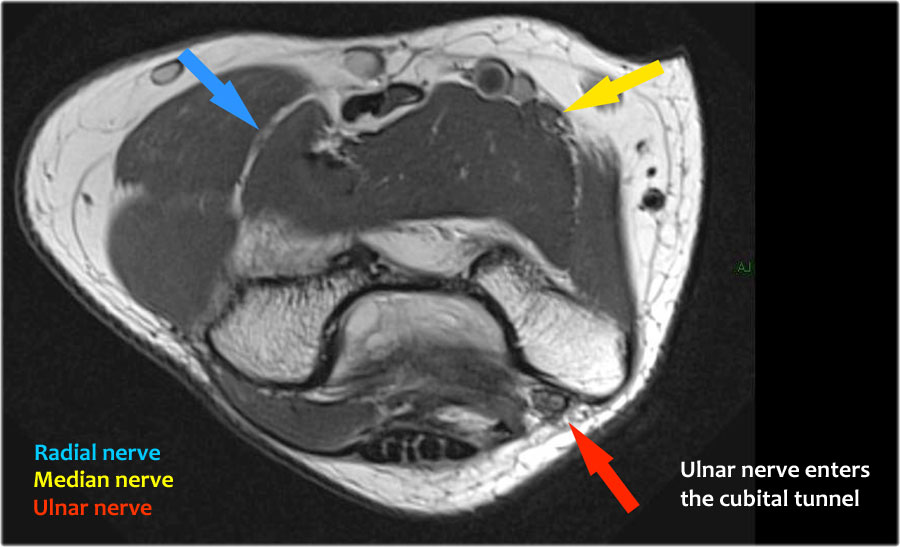

Scroll through the images.

Ulnar nerve

Ở đây chúng ta thấy dây thần kinh trụ nằm trong ống trụ.

Bó sau của dây chằng bên trụ tạo thành sàn của ống, trong khi mạc hãm tạo thành trần của ống.

Radial nerve

Dây thần kinh quay có thể được xác định rõ nhất ở mức chỏm xương quay, nơi có thể quan sát thấy các nhánh nông và nhánh sâu trong ống xương quay (mũi tên).

This is a very consistent place to find the radial nerve.